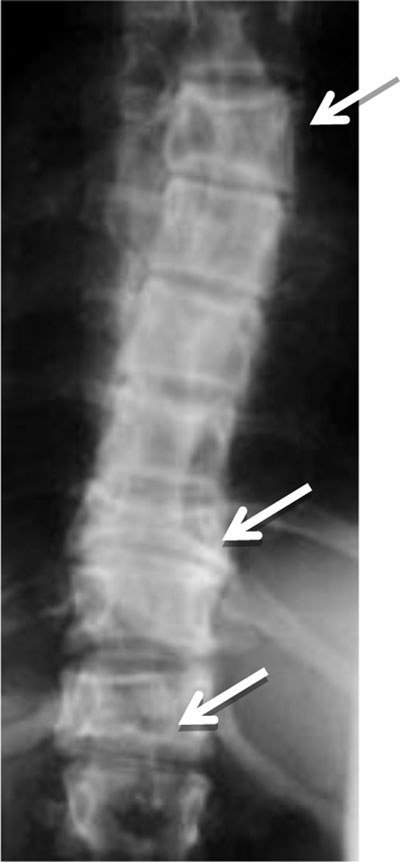

Figure 8

Polyostotic Fibrous Dysplasia. Radiograph shows collapse of multiple vertebral bodies (T6, T10, T12) with a ground glass matrix.